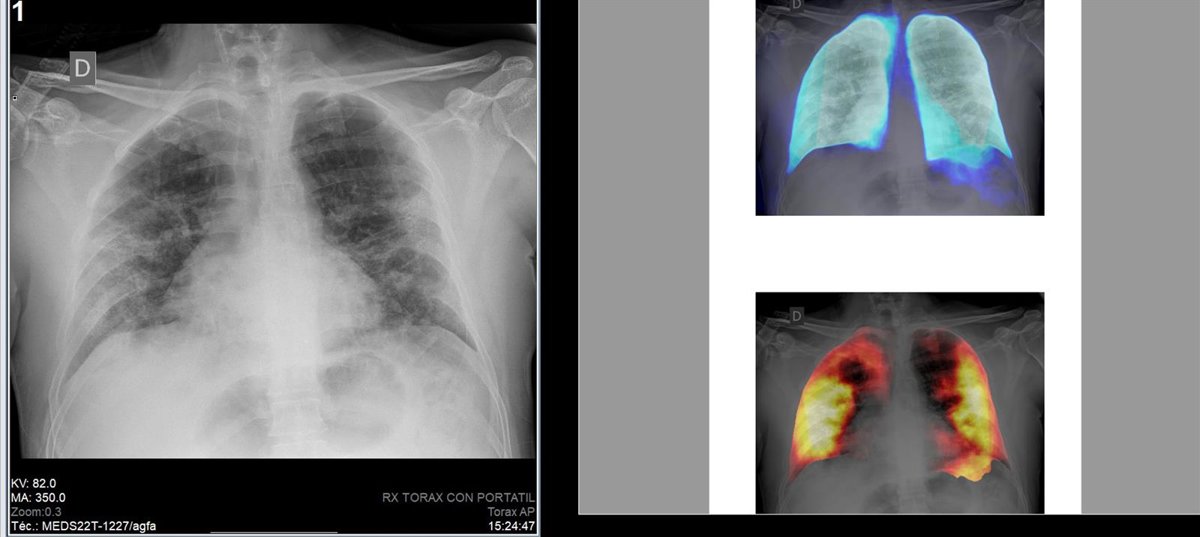

Organizan un "desafío" para detectar y localizar Covid mediante inteligencia artificial en radiografías de tórax

La Society for Imaging Informatics in Medicine (SIIM), en colaboración con la Fundació per al Foment de la Investigació Sanitria i Biomdica de la Comunitat Valenciana (Fisabio) y la Sociedad Radiológica de Norteamérica (RSNA), ha organizado un "desafío" para la detección y localización de neumonía por Covid-19 mediante el uso de la Inteligencia Artificial en radiografías de tórax.

El desafío científico utilizará conjuntos de imágenes de radiografías convencionales de la Medical Imaging Data Resource Center (MIDRC) - RSNA International Covid-19 Open Radiology Database (RICORD) y del Banco de Imagen Médica de la Comunidad Valenciana (BIMCV-COVID-19 Dataset). El dataset fue entregado en formato MIDS (Medical Imaging Data Structure).

Las personas participantes en el desafío desarrollarán modelos de computación de alta calidad para detectar y localizar la neumonía por la Covid-19 para ayudar a los médicos a proporcionar un diagnóstico rápido y seguro que mejorará la atención del paciente al permitir un tratamiento adecuado antes de que aparezcan los efectos más graves del virus.